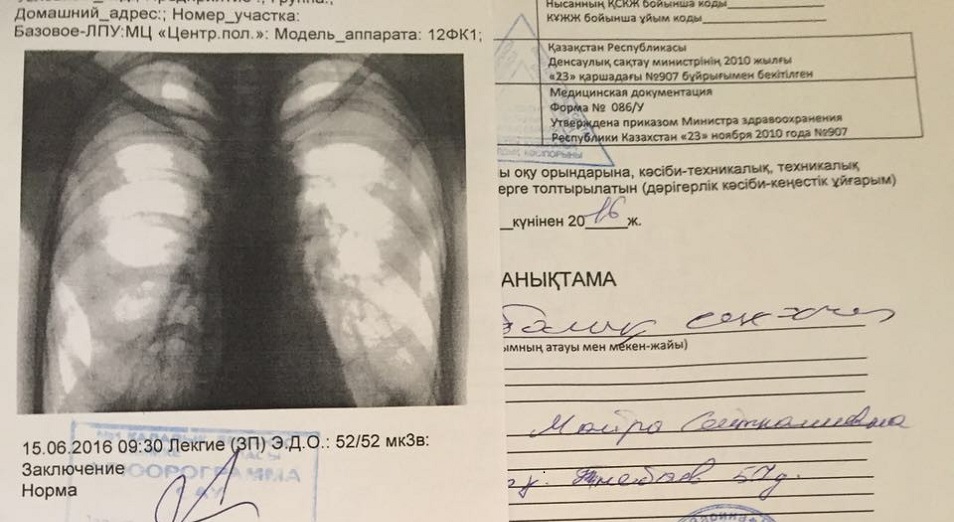

Фотографии рентгеновских снимков без необходимости направления от врача